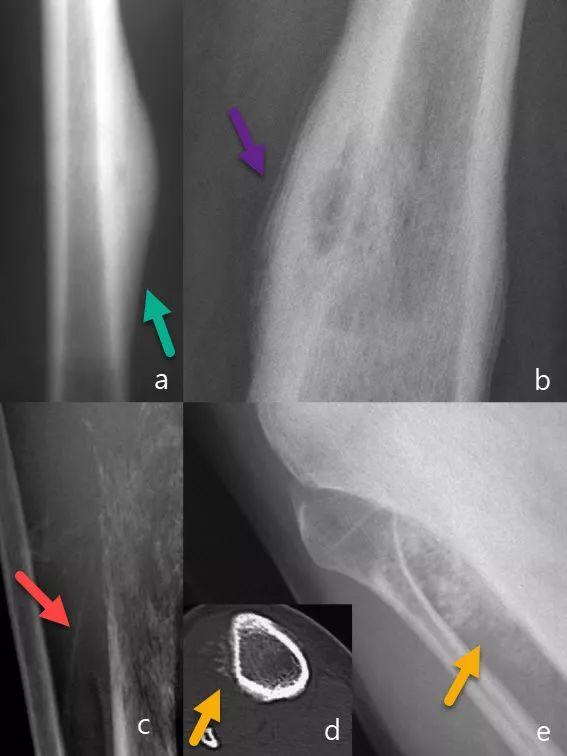

骨膜反应Periosteal reaction::当存在骨膜刺激时发生。原因是良性、恶性肿瘤,感染或创伤(图4)。

1、实变或连续骨膜反应:良性,生长缓慢的病变。

2、中断的骨膜反应:急性反应,没有时间进行巩固。

图4:骨膜反应。厚实的骨膜反应(绿色箭头)(a)。多层骨膜反应(紫色箭头)(b)。骨肉瘤中断骨膜反应和Codman三角形(红色箭头)(c)。Spiculated骨膜反应(黄色箭头)(d和e)。